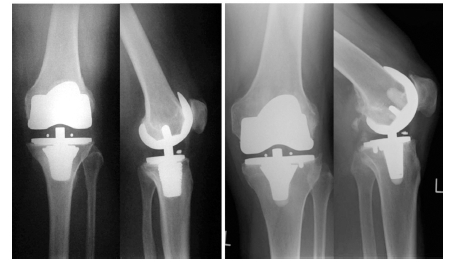

The company ORTHOPEDIC NIKIFOROV was founded in 1998 by the candidate of medical sciences. doctor of orthopedic-traumatologist of the highest category Nikiforov IA Owing to high professionalism and results of work, ORTONIC has gained well-deserved reputation and reputation among colleagues and population of Dnepropetrovsk region and CIS countries (Russia, Moldova, Armenia, etc.). The principle of the enterprise is NO IMPOSSIBLE, it is based on knowledge, experience and active implementation of modern technologies in orthopedics and traumatology. Conservative methods of treatment include individual selection of medicines, therapeutic blockades, manual therapy, massage, physiotherapy (vibration table, magnetotherapy, bioptron, electromyostimulation, etc.), rehabilitation with the suggestion of the necessary concomitant devices and means for the fastest recovery (corsets, bandages, various joint fixators, crutches, walking sticks, etc.). Various minor invasive interventions (chymonucleolysis, vertebroplasty, kyphoplasty, percutaneous nucleoplasty using cold plasma) that are performed on an outpatient basis are successfully used to treat problems associated with spine pathology. The latest modern treatment methods introduced in our company are endoscopic operations using the TYSSES technique of Joimax (Germany) with intervertebral hernias, stenosis and other pathologies of the spine, which allow to avoid complications occurring during open operations and the accompanying general anesthesia. We have many years of successful experience in traditional and modern minimally invasive endoprosthetics of large and small joints, which remains the main direction of our activity. Our company is the exclusive representative of the German company IO International Orthopaedics Holding GmbH, which based on the already known prostheses, its ideas and technological capabilities, has developed and implemented a new concept in hip replacement - an artificial joint prosthesis (ICON). We assist interested colleagues in training the operative technique for installing an artificial joint prosthesis - ICON, both in the workplace and in Germany. For 20 years we have been successfully cooperating with Sanitatshaus Gerd Klinz ortho team, an enterprise that for 20 years has been one of the leading places in Germany for the production of functional prostheses of the upper and lower limbs, as well as cosmetic prostheses of limbs and other body parts (nose, ears, eyeballs, fingers). We have an atmosphere of friendliness and human participation. Politeness, benevolence, the desire to understand and help is the basis of our attitude towards patients. We are always glad to see you and will do our best to make you feel great! We are waiting for you at: Ukraine, Dnepr, Gagarin Ave., 13 (under reconstruction) on all questions to address: tel .: +38 (050) 488-88-92 E-mail: orthonik.ukr@gmail.com Germany, Spine Nano Klinik, Zeppelinstr. 21, Potsdam Tel. +4901801121919 E-mail: kmw.nikiforov@hotmail.de